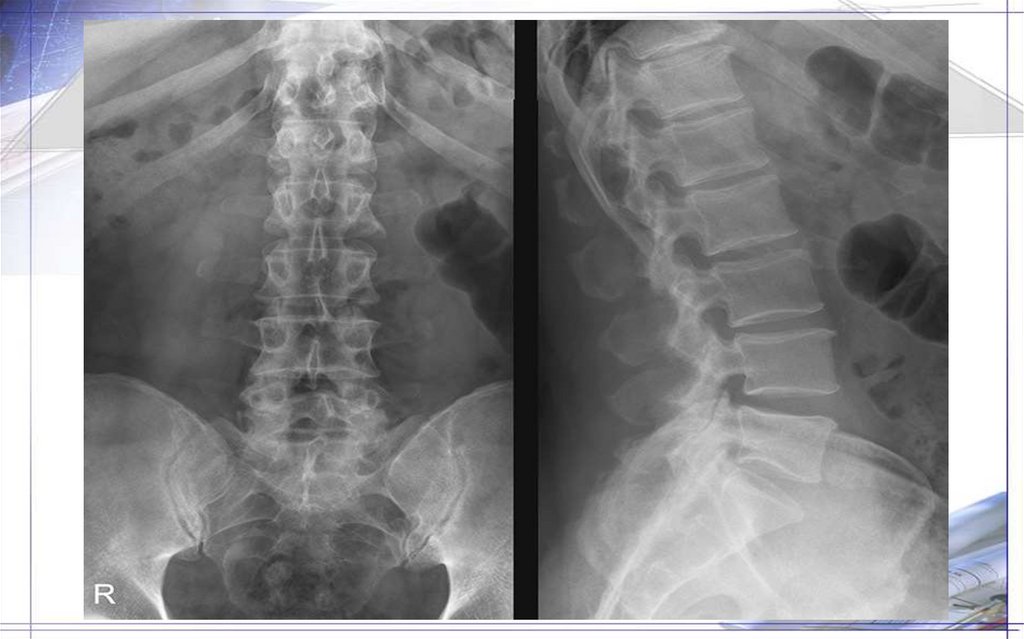

Поясничные позвонки(5):

-тела позвонков бобовидной формы, массивные

-дуги сильно развиты

-позвоночное отверстие больше, чем у грудных позвонков

-позвоночное отверстие неправильной треугольной формы

-поперечные отростки впереди суставных, удлинены, сжаты спереди назад, идут латерально и несколько назад

-большая часть поперечного отростка –реберный отросток(рудимент ребра)

- на задней поверх-ти основания реберного отростка –добавочный отросток-рудимент поперечного отростка(короткий,

широкий.утолщен, закруглен на конце)

-суст.отростки идут кзади от поперечных и располагаются почти вертикально

-суст.поверх-ти в саггитальной плоскости(вогнутая верхняя медиально, выпуклая нижняя латерально)-суст.отростки одного

позвонка охватывают с боков нижние суст.отростки другого позвонка

-на задне-наружном крае верхнего суст.отростка-небольшой сосцевидный отросток(прикрепление мышц)

18. Особенности поясничных позвонков